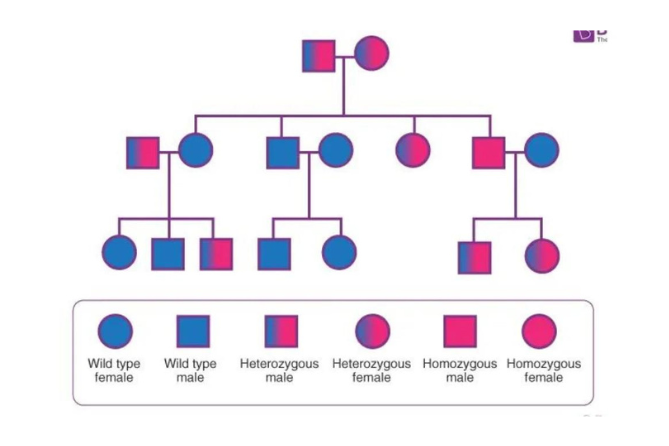

Fetal Genetics

Stay current with advanced genetic testing. Provide informed counseling & empower patient choices.